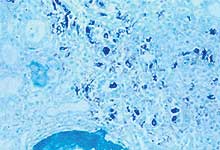

"Hibridación in situ" para la detección de genoma de PCV2 en el riñón de un cerdo afectado de síndrome de dermatitis y nefropatía porcino. Las células coloreadas en azul corresponden básicamente a macrófagos que contienen ácido nucleico de PCV2.